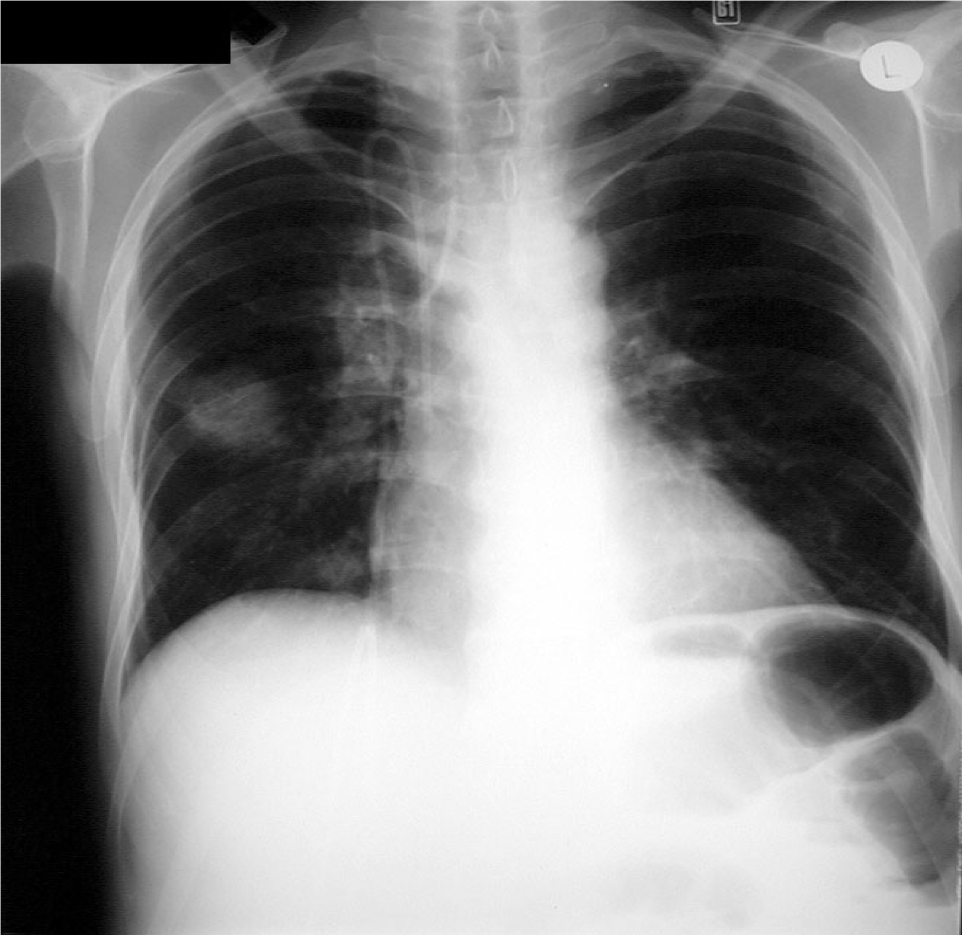

Fungal pneumonia in AML-CXR

Area of consolidation on right side